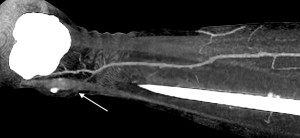

Пацієнти та методи. Відповідно до мети роботи було проаналізовано дані обстеження 46 пацієнтів, що знаходилися на стаціонарному лікуванні в опіковому відділенні КЗ «Дніпропетровська міська клінічна лікарня №2 ДОР» з глибокими локалальними ушкодженнями нижніх кінцівок в період з 2009 по 2015 рік, і яким було виконано 54 оперативних втручань із використанням локальних перфорантних клаптів з живлячою ніжкою, що включала одну домінантну перфорантну артерію. Пацієнти були розділені на дві групи. В групу 1 (контрольну) було включено 25 пацієнтів (29 оперативних втручань) у яких стандартне обстеження включало локацію перфорантів за допомогою аудіо-доплера «Мінідоп» з датчиком 8 MHz. Передбачуване місце вихода перфоранта та його напрямок позначалися на шкірі пацієнта за допомогою маркера [10,12]. (Мал. 1). В групу 2 було включено 21 пацієнта (25 оперативних втручань) у яких стандартне передопераційне обстеження було модифіковане за рахунок контрасної КТ-ангіографії [8,7] з обробкою візуальних карт судинної системи в зоні втручання програмою ”Osirix” (Мал. 2).

Мал. 2. Контрасна КТ-ангіографія з обробкою візуальної карти судинної системи нижньої кінцівки в зоні втручання програмою ”Osirix”. Точку виходу перфрантної артерії в шкіру над кісточкою – відзначено стрілкою.